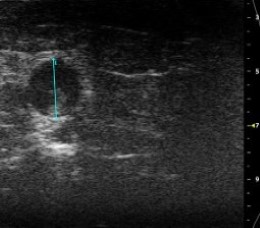

- in vivo VisualSonics Vivo 2100 vascular imaging

- Aortic Harvest with ex vivo measurement of aortic diameter

Abdominal Echo's performed 24 hours prior to sac using VisualSonics Vivo 2100